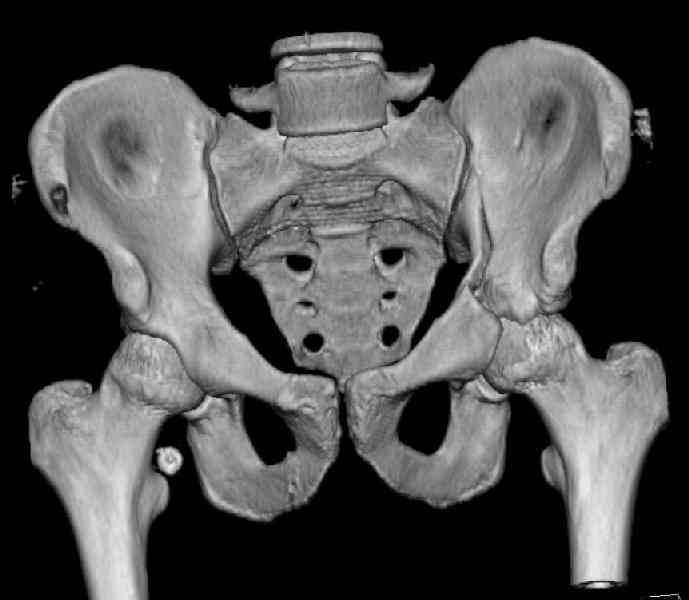

The last two images from the 3-D CT scan certainly makes the fracture look worse than the plan radiographs.

The joint is non-concentric as the head appears to be either "following the caudal segment", or the dome component is displaced from the tethered head... or so it seems... and he's young... so, many fracture surgeons would recommend reduction and fixation.

Some more images. Does it help to guess which part of the acetabulum is displaced?

Normal appearing SI joints and a healed posterior column limb... my bet's on caudal segment displacement.